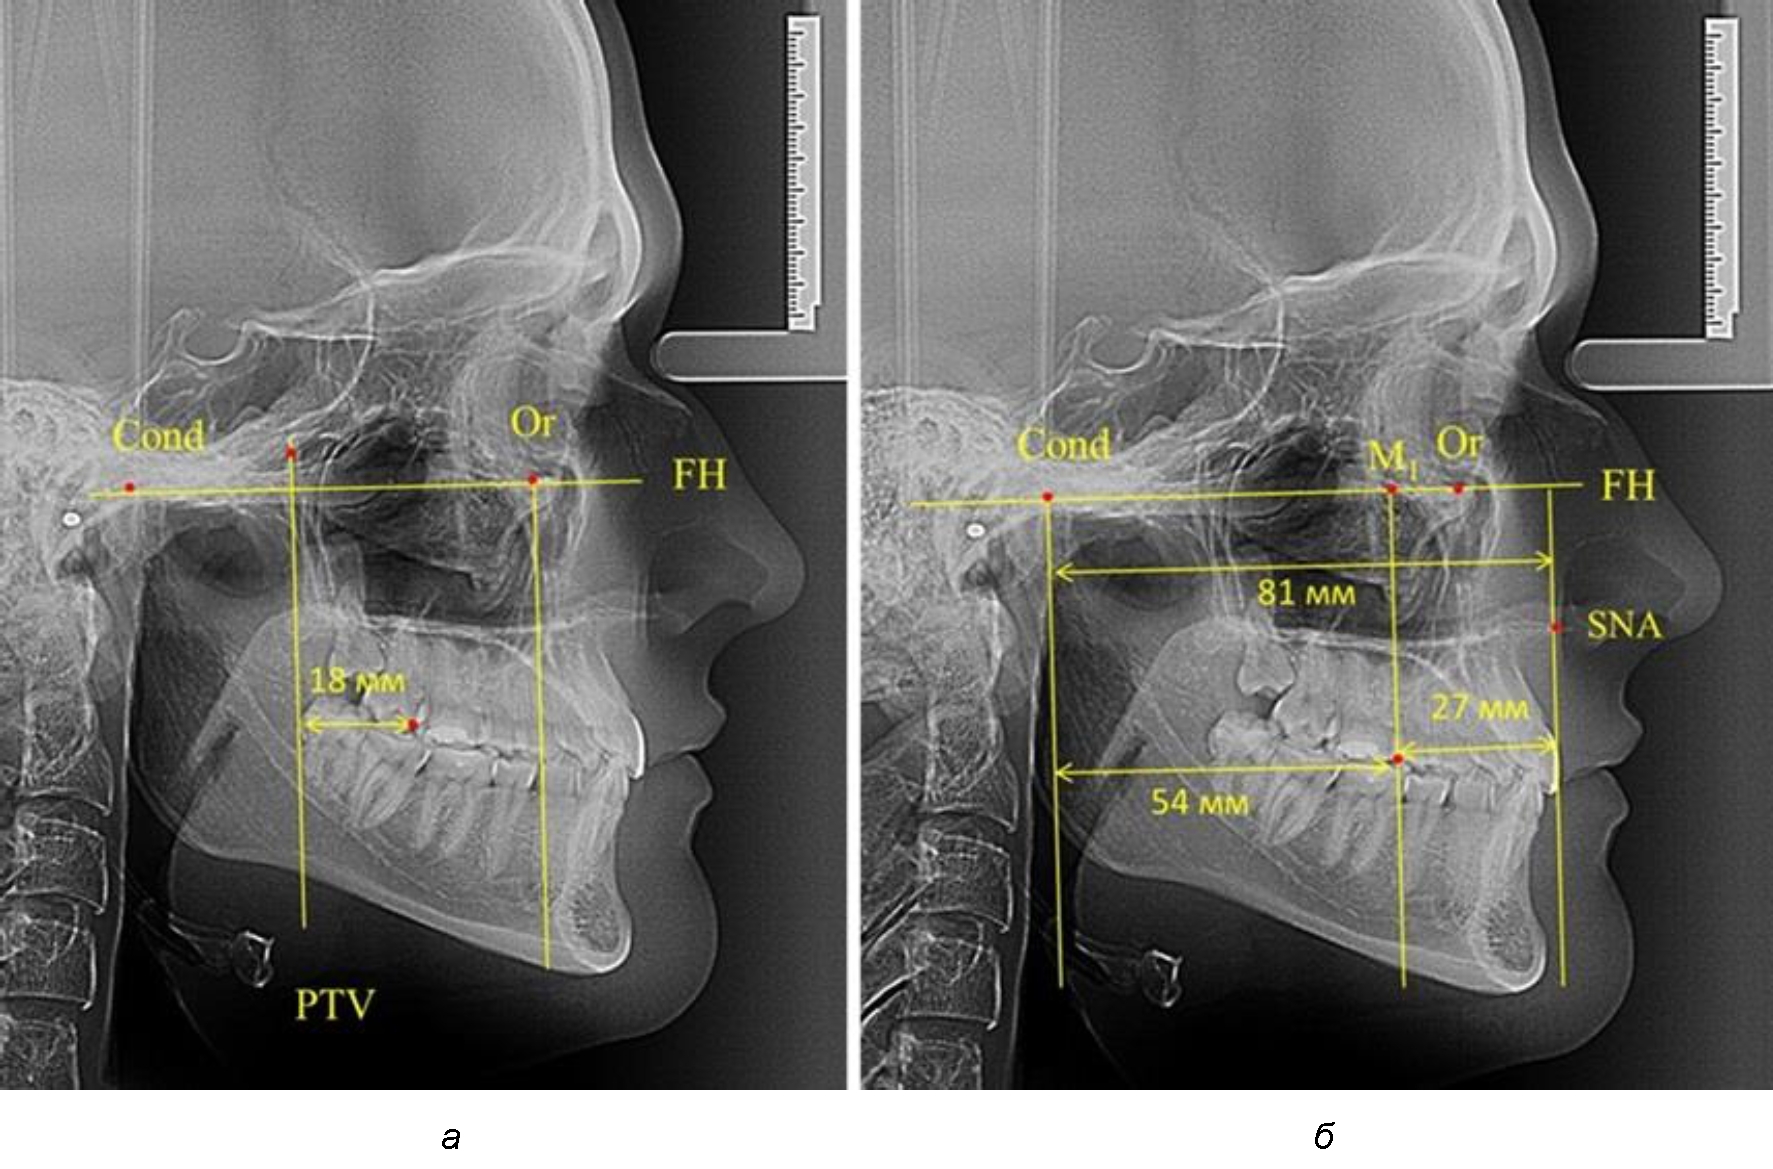

Таким образом, для прогнозирования оптимального положения первых постоянных моляров наиболее целесообразным методом явилось использование относительного показателя, что подтверждено при анализе рентгенограмм с минимальными и максимальными значениями по методу R. E. McDonald.

Так, при расстоянии от крыловидной вертикальной плоскости PTV до дистальной поверхности верхнего первого постоянного моляра в 13 мм сагиттальный размер гнатического отдела был 82 мм. При этом отношение кондилярно-спинального расстояния к кондилярно-молярному размеру (54,5) было близким к коэффициенту 1,5, что представлено на рис. 2.

Рис. 2. Особенности положения первых моляров по R. E. McDonald (а) и по предложенному методу (б) при уменьшенном молярно-крыловидном расстоянии